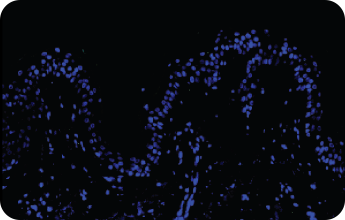

인체 피부조직에서의 흡수도 평가

Normal

Control Group

Test Group